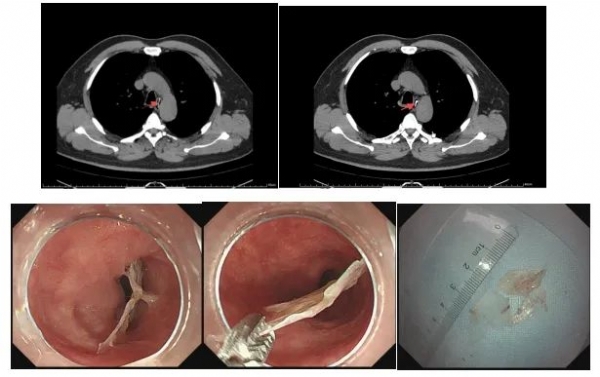

近日,脾胃病科来了一位胸骨后疼痛的患者,患者在喝汤的时候误吞了鱼骨,胸部CT提示食管平主动脉弓水平见不规则致密影,最大矢状径约2.7cm,前后径约为2.1cm,局部与管壁关系密切。考虑邻近主动脉弓,异物在此处造成穿孔后,容易引发大出血,危及生命,立即安排急诊胃镜。在赵月坤主任的指导下,脾胃病科秦兴平医师与内镜室护士、麻醉医师密切配合,行急诊胃镜食管异物取出术。术中见距门齿约30cm可见一不规则异物嵌顿,部分刺入黏膜,局部充血水肿,见少量渗血,未见明确穿孔。通异物钳取出,异物大小约2.5×4cm。术后患者安全返回病房,成功为患者解除痛苦,精湛的技术赢得患者及家属赞誉。